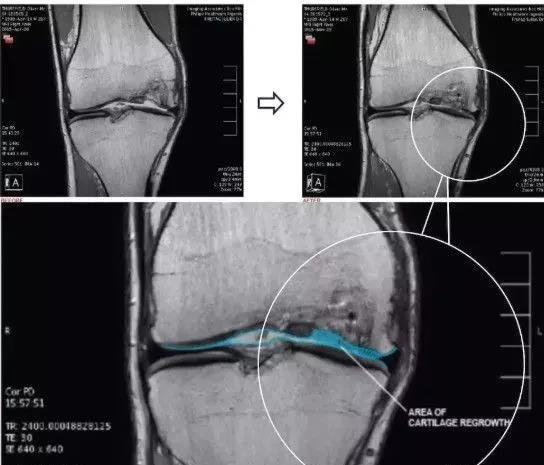

ÁíÒ»ÏîÖ¬·¾¸Éϸ°ûÖÎÁÆÏ¥¹ÇÐԹؽÚÑ×µÄÁÙ´²ÁÆÐ§¼°¶þÆÚ¹Ø½Ú¾µ¼ì²é¡£Ñо¿ÈËÔ±·Ö±ðÏò30Àýƽ¾ùÄêÁäΪ65ËêÀÏÄ껼ÕߵĹؽÚÇ»ÄÚ×¢É䯽¾ùֵΪ4.0¡Á106¸Éϸ°û£¬Ëæºó½øÐÐÁË2ÄêµÄËæ·Ã¡£Ê®ÁùÀý»¼ÕßÔÚ´ËÆÚ¼ä½øÐÐÁ˵ڶþ´Î¹Ø½Ú¾µ¼ì²é£¬¼¸ºõËùÓл¼Õß¾ùÓÐÃ÷ÏÔ¸ÄÉÆ£¬ÆäÖÐ87.5%µÄÀÏÄ껼Õ߸ÄÉÆ»òά³ÖÈí¹Ç״̬ÖÁÉÙ2Äê¡£¶øÇÒ£¬Ã»ÓÐÒ»¸ö²¡È˽ÓÊܹýÔÚÕâ2ÄêÆÚ¼ä½øÐÐȫϥ¹Ø½ÚÖû»Êõ¡£

ÉÏͼaΪÖÎÁÆÇ°¹Ø½Ú¾µ¼ì²é½á¹û£¬¿ÉÒÔ¿´³öÈí¹Ç´æÔÚȱËð¡£Í¼bΪ֬·¾¼ä³äÖʸÉϸ°ûÁªºÏPRPÖÎÁÆ£¬Í¼cΪÖÎÁƺó½á¹û£¬Èí¹ÇµÃµ½ÁËÐÞ¸´¡£